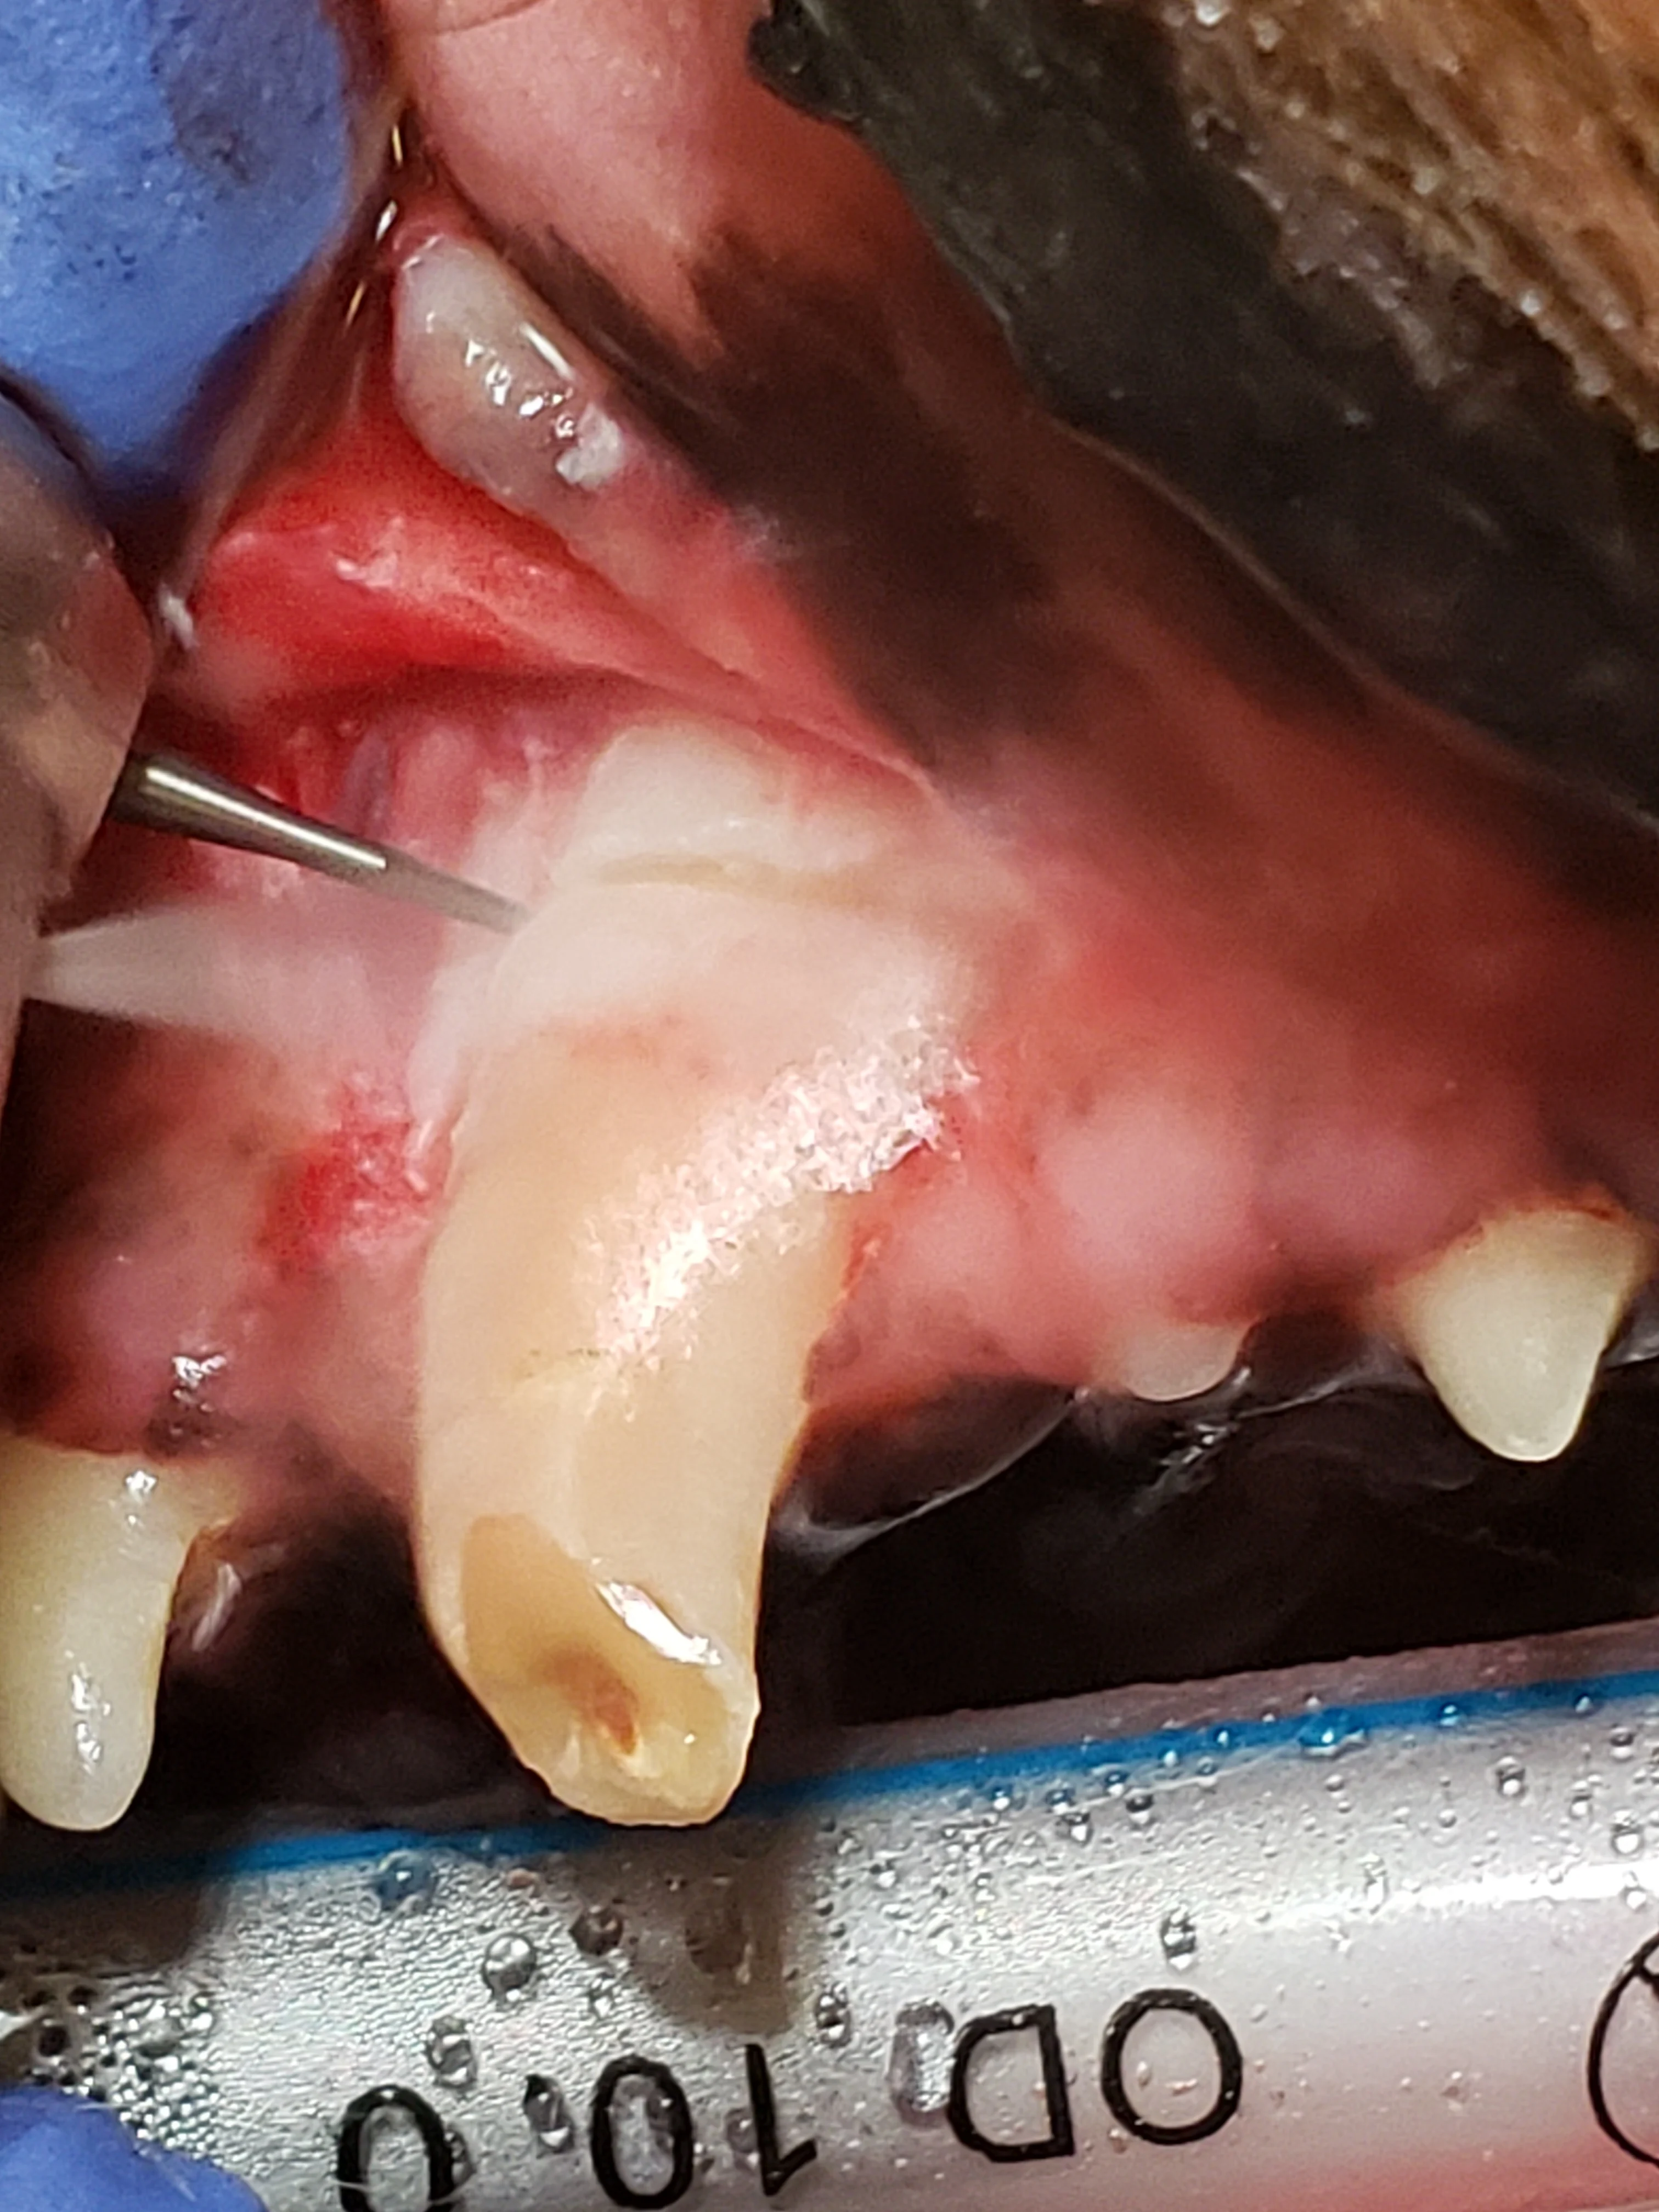

Step 5: Alveolar Bone Removal

Use a round, pear-shaped, or crosscut fissure bur to create grooves at the mesial and distal aspect of the root, at least to the level of the widest part of the root.

Author Insight

Bone removal is performed to provide adequate exposure, form an exaggerated periodontal ligament space following the root contours, and provide an opening for easier root elevation. A pear-shaped or round bur may be preferred for creating these grooves in the periodontal ligament space, as a crosscut bur can be too aggressive if used incorrectly.

Making a cut in the bone at the widest part of the root can help delineate the area in which buccal bone can be removed. A coarse diamond-cut bur is sometimes preferred to remove this buccal bone.